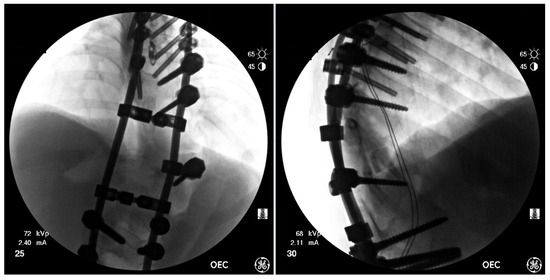

Figure 7.

AP & Lateral fluoroscopy images of temporary spinal instrumentation stabilization.

Three rods were then cut, contoured to the desired shapes in the sagittal and coronal planes, and fastened to the screws. On the left side, side-to-side connectors were used to connect two rods in the thoracic and lumbar spine, while on the right side, a transition rod was contoured and it spanned the entire congenital segment. Strategic distraction, compression and de-rotation were used to achieve correction (Figure 7). Throughout the procedure, spinal cord monitoring revealed strong MEPs to the quadriceps but no recovery of MEPs below the knees.

After close overnight monitoring in the ICU, and noting positional response to motor function, the patient was returned to the OR for temporary spinal stabilization through the previous midline incision from T5 to L4. Using intraoperative CT imaging, with the T8 sublaminar wire as a fiducial marker, accurate registration was achieved for the placement of pedicle screws under robotic guidance from T5–T9 with solid purchase. The robotic platform was not able to accurately register screws from T10–L2, so the 3D model was used to guide manual implantation of right-sided L2–L4 screws.